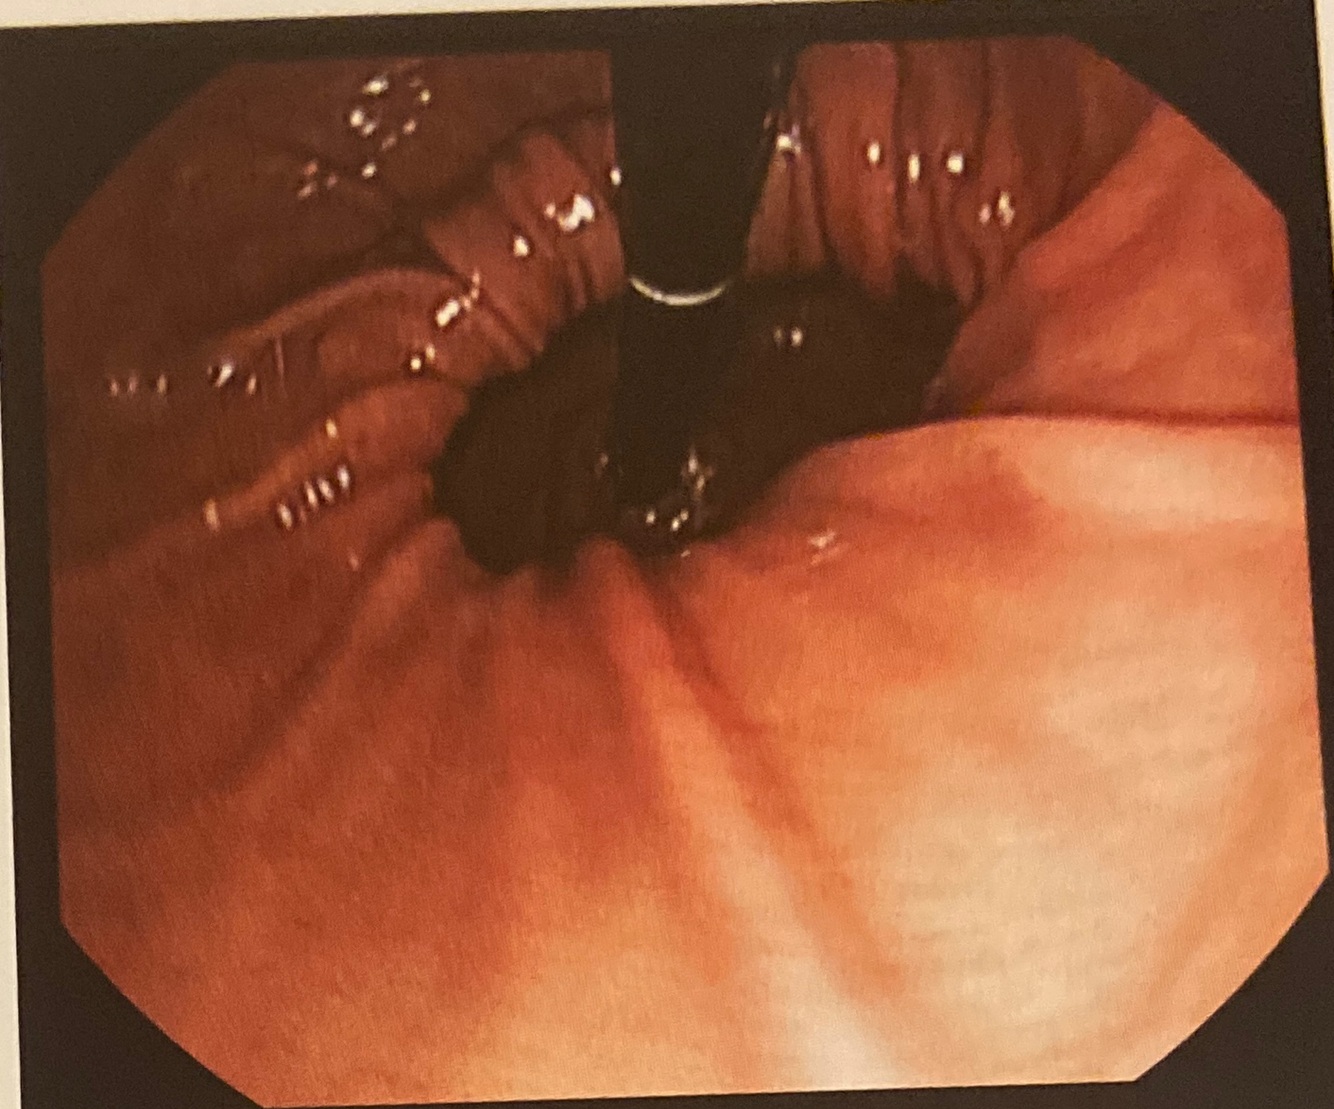

A

A manobra da retrovisão da cárdia evidencia alargamento do hiato diafragmático